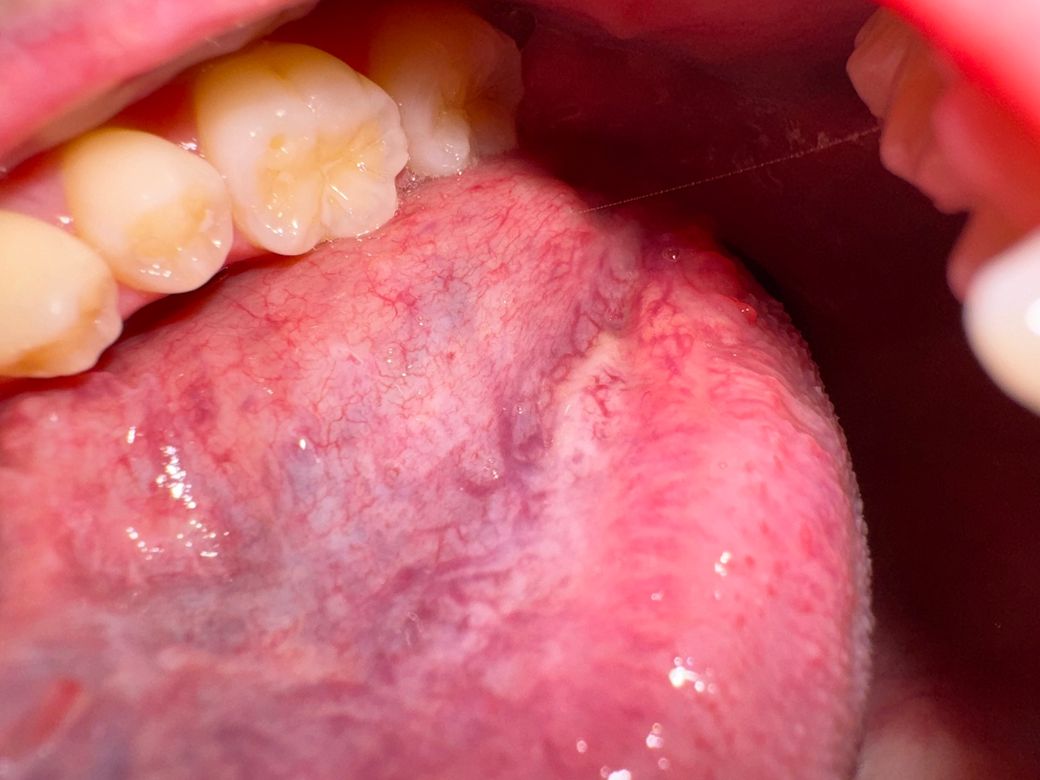

설암 초기증상인지 백반증인지 정상조직인지...ㅠㅠ

26세 남성입니다ㅠㅠ

아이코스 전자담배를 흡연하고있고

흡연한지는 7년째인데

백반증이나 설암 초기증상인건가요? ㅠㅠ

전혀 아프지도않고

우연히 혀 밑을 봤는데 사진들처럼 하얘져있어서 자꾸 신경쓰여서요ㅠㅠ

일단 일부 사진과 질문자님의 증상만으로 의견을 말씀드리자면, 약간의 덩어리가 하얗게 발생한 것으로 보이며 덩어리진 양상이 만져진다면 백반증일 가능성이 있어보이며, 설암의 경우 출혈이나 통증이 동반되는 경우가 많아 약간은 가능성이 떨어집니다.

다만 정확한 진단의 경우 치과에 가셔서 의사의 진찰 및 필요시 조직검사를 받으시는 것이 좋겠습니다.